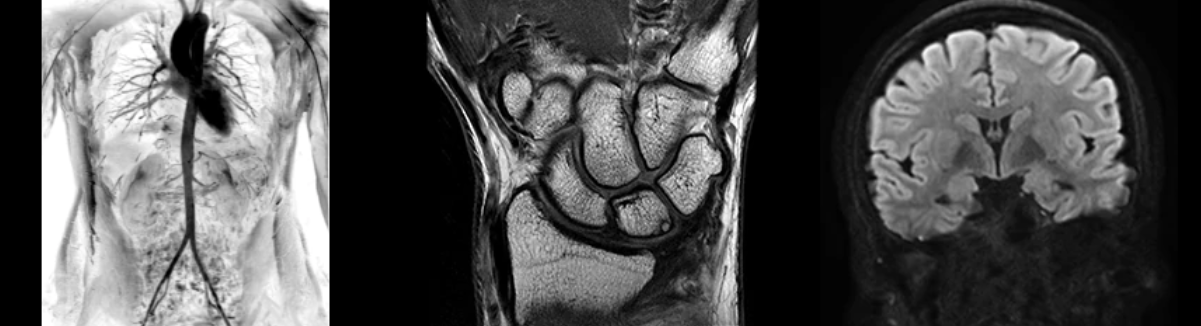

- NeuroWorks

Представляет собой универсальное решение для визуализации анатомии головного мозга, позвоночника, сосудов и периферических нервов с четкой дифференциацией тканей.

- OrthoWorks

Программное решение OrthoWorks разработано для визуализации структур опорно-двигательного аппарата с прекрасным контрастированием тканей.

- BodyWorks

Используйте BodyWorks для визуализации абдоминальной и тазовой областей с учетом любых типов пациентов.

- OncoWorks

Включает клинические приложения для обработки и визуализации анатомических и морфологических данных, специфичных для каждого типа онкологических образований.

- CVWorks

Приложение для кардиовизуализации, с помощью которого вы сможете получить данные о морфологии, динамике кровотока, функции миокарда, а также информацию о структуре сосудов.